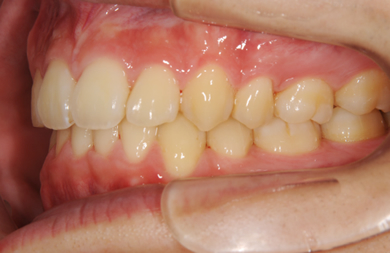

| 性別/年齢 | 男性 / 24歳 | ||||||||||||||||||||||||||||||||

| 主訴 | 乱ぐい歯を治したい。 | ||||||||||||||||||||||||||||||||

| 治療方針 | 歯のがたつきが大きいことより上下左右第一小臼歯を抜歯して、マルチブラケット装置にて治療。また、親不知がまっすぐ生えることができず横を向いている状態なので、まっすぐにする隙間があることから親不知も使用し、矯正を行う。 | ||||||||||||||||||||||||||||||||

| 治療内容 | 唇側矯正(ホワイト) | ||||||||||||||||||||||||||||||||